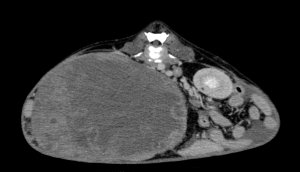

今回治療させていただいたワンちゃんは、ここ1年ほどでお腹が張ってきており、散歩中に立てなくなったとの事で来院されました。原因は、巨大な脾臓腫瘍と、脾臓腫瘍から壊死物質が漏れたことによる腹膜炎でした。重度の貧血を呈していたため、輸血で状態を安定化し、翌日に手術を行いました。脾臓腫瘍は、直径20センチ、重さ2.7kgで、病理組織学的検査は「脂肪肉腫」でした。幸いなことに、手術前のCT検査で転移所見はありませんでした。